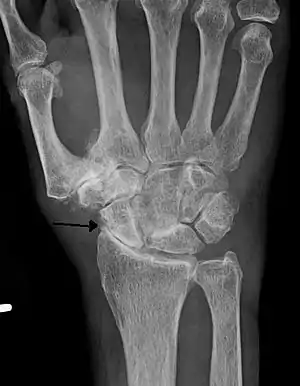

Severe osteoarthritis and osteopenia of the carpal joint and 1st carpometacarpal joint